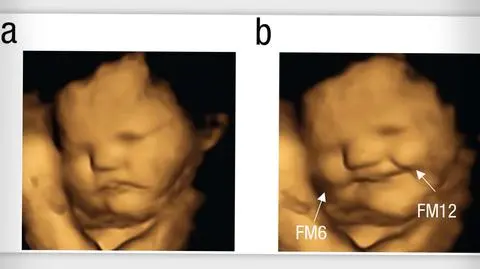

20 minut po podaniu kapsułek z warzywami ciężarne kobiety były badane przy pomocy USG. Na zdjęciach ich nienarodzonych dzieci zaobserwowano, że większość z tych, których matki zjadły jarmuż, wydawała się "grymasić". Z kolei większość z tych dzieci, których matki otrzymały marchewkę, wydawała się uśmiechać. U dzieci z grupy kontrolnej kobiet, które nie zjadły żadnego z tych warzyw, nie zaobserwowano żadnych reakcji.

Źródło: Beyza Ustun/Durham University

- Udało się nam jako pierwszym pokazać na zdjęciach USG mimikę twarzy, która pojawia się po kontakcie z żywnością, którą właśnie spożyła matka - powiedziała Nadja Reissland, współautorka badania i szefowa Fetal and Neonatal Research Lab na Durham University.

Według niej na zdjęciach zauważono podobne reakcje jak u dzieci i dorosłych po zjedzeniu czegoś gorzkiego. Jak zaznaczyła, między 24. a 36. tygodniem ciąży mimika twarzy nienarodzonych dzieci staje się coraz bardziej złożona.